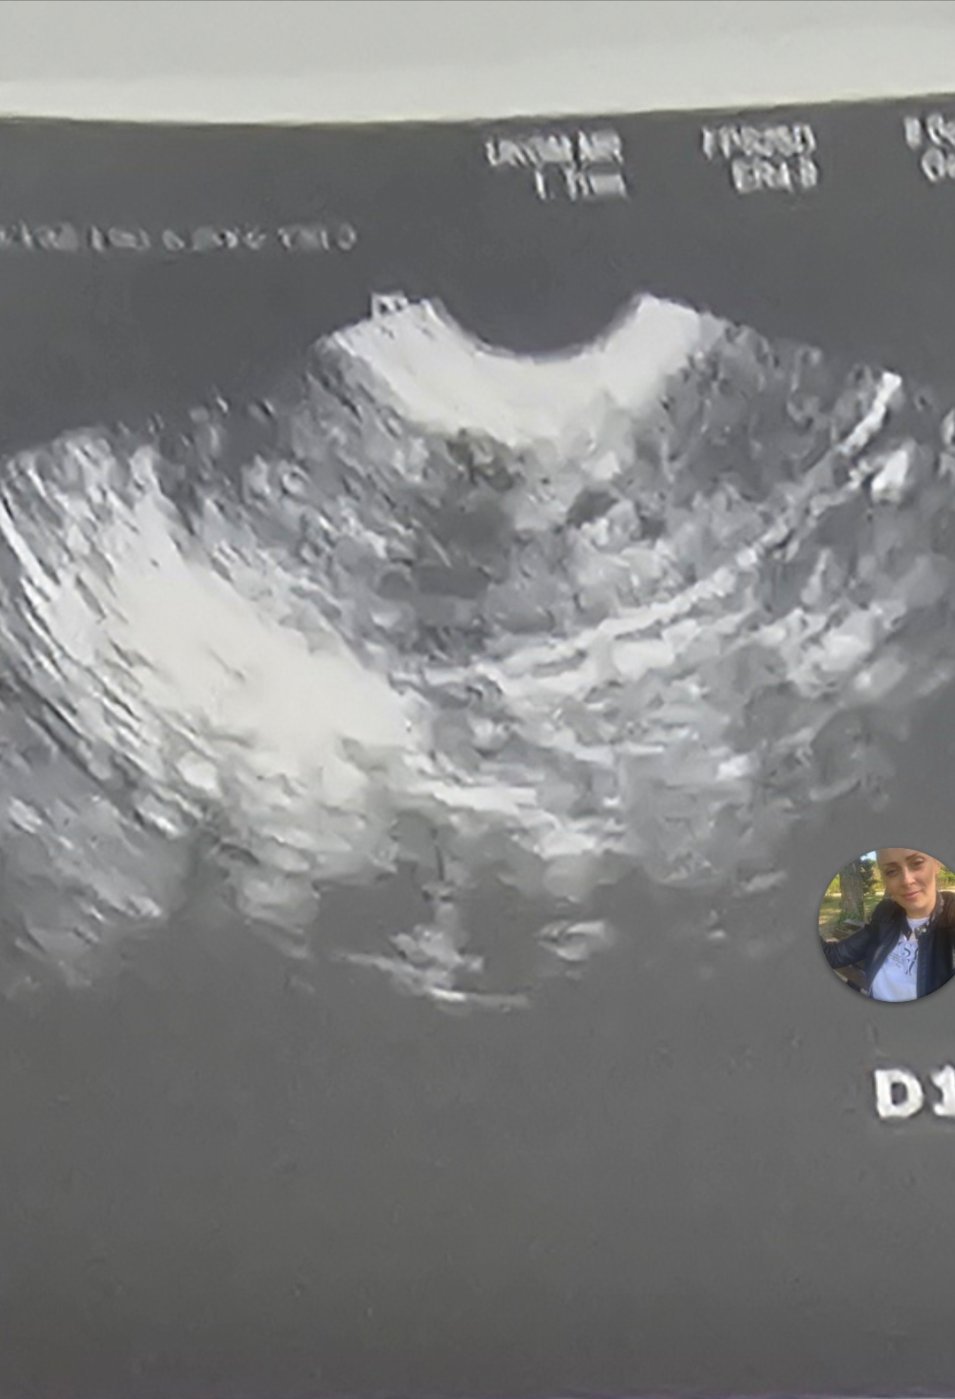

Какво представлява изображението от ехографията на 5-седмична и 2-дневна бременност?

Какво представляват белите точки в плодния сак на ехографската снимка?